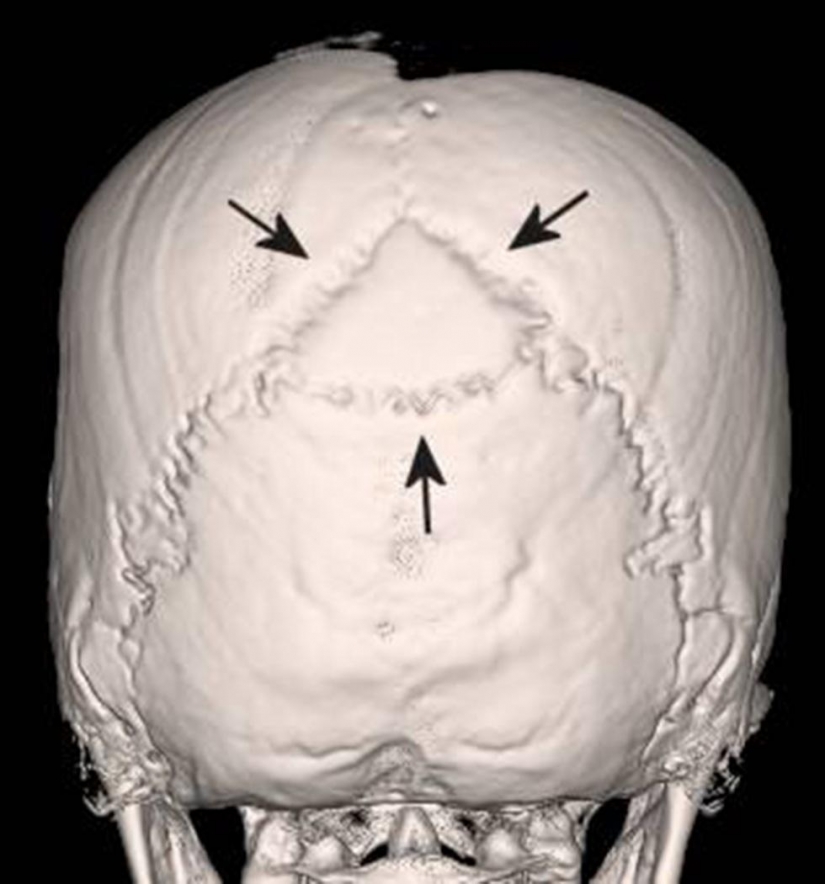

13. Su cráneo fue también característico de la "variedad" de los huesos que sólo las Naciones de América del Sur, pero no Europeos.

14. Por un lado la cara de la momia parecía bastante normal, pero en el interior de su cráneo, los huesos estaban rotos.

15. Como se puede ver, la parte frontal de su cráneo está completamente fracturado.